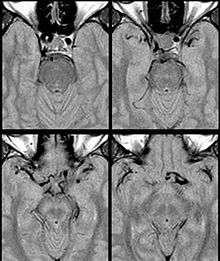

Fig. 1: Dolichoectasia of the suprasellar segment of the left internal carotid artery with compression of the optic chiasm

Internal Carotid Artery dolichoectasia is particularly interesting because the artery normally already contains one hairpin turn. Seen in an MRI as two individual arteries at this hairpin, a carotid artery dolichoectasia can progress so far as to produce a second hairpin turn and appear as three individual arteries on an MRI. In the case of a dolichoectasia of the Internal Carotid Artery (ICD), the pathogenesis is primarily related to compression of the Optic Nerves at the Optic Chiasma (see Fig. 1 and 2).